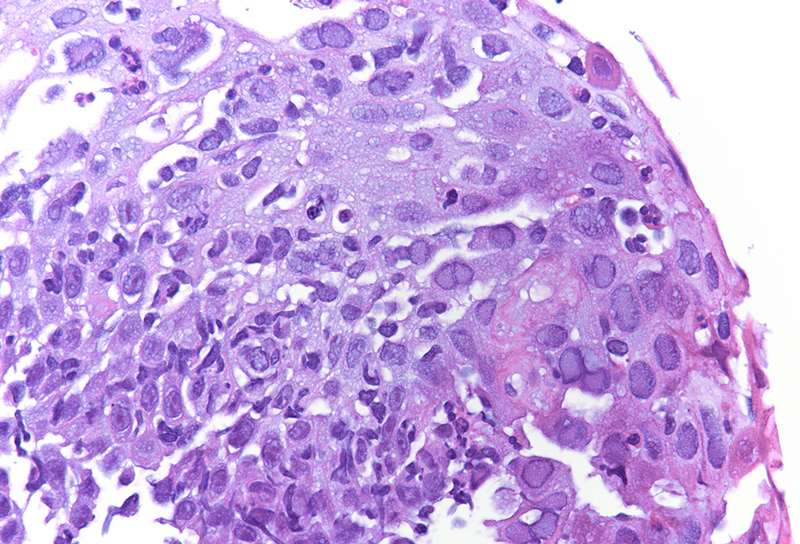

Cytology disclosed groups of squamous cells with enlarged ground-glass nuclei with homogenous chromatin pattern and multinucleation (Panels C-D). Upon histology, we observed multiple fragments of squamous epithelium with degenerating features admixed with inflammatory detritus. The nuclei of the squamous cells displayed ground-glass morphology as documented in the cytological material (Panels E-F). Immunostaining for Herpes simplex virus (HSV) I and II was positive (Panels G-H).

Histologically, the virus infects oesophageal squamous epithelium, typically at the superficial lateral margin of ulcers and erosions. The morphological diagnostic criteria include: (i) dense intranuclear eosinophilic to amphophilic round inclusion bodies with a clear halo separated from the nuclear membrane (Cowdry A inclusions), (ii) ground-glass nuclei with homogenous chromatin pattern, (iii) nuclear molding, (iv) multinucleated syncytia giant cells and (v) detached ballooning degeneration of infected cells. Immunohistochemistry studies is helpful in equivocal cases.